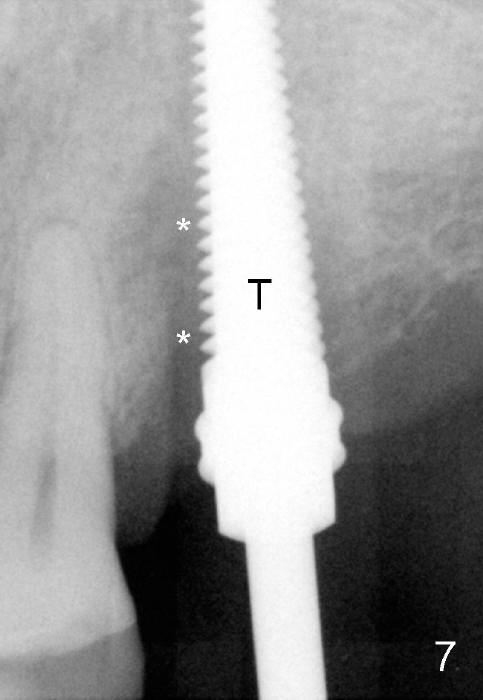

Fig.5 is an illustration showing the socket after extraction. The osteotomy is intentionally placed distally (Fig.6 arrow: pilot drill). In case the patient agrees to have ortho treatment, there will be space to correct the upper midline (7). If not, a molar crown will be fabricated. By the time a 4.5x20 mm tap is inserted (Fig.7 T), the mesial gap is visible (*). When a 6x20 mm implant is placed (Fig.8 I), bone graft is placed buccally (Fig.2, as planned) and mesially (Fig.8 red circles, as compared to Fig.1). The implant has to be as large and long as 6x20 mm to get primary stability (insertion torque 50/60 Ncm). The apex of the implant is close to the sinus floor (Fig.8 ^) or in fact the nasal floor (Fig.9 N). There appears bone growth in the mesial gap 3 months postop (Fig.10 *). There is no bone loss 2.5 years post cementation (Fig.11).